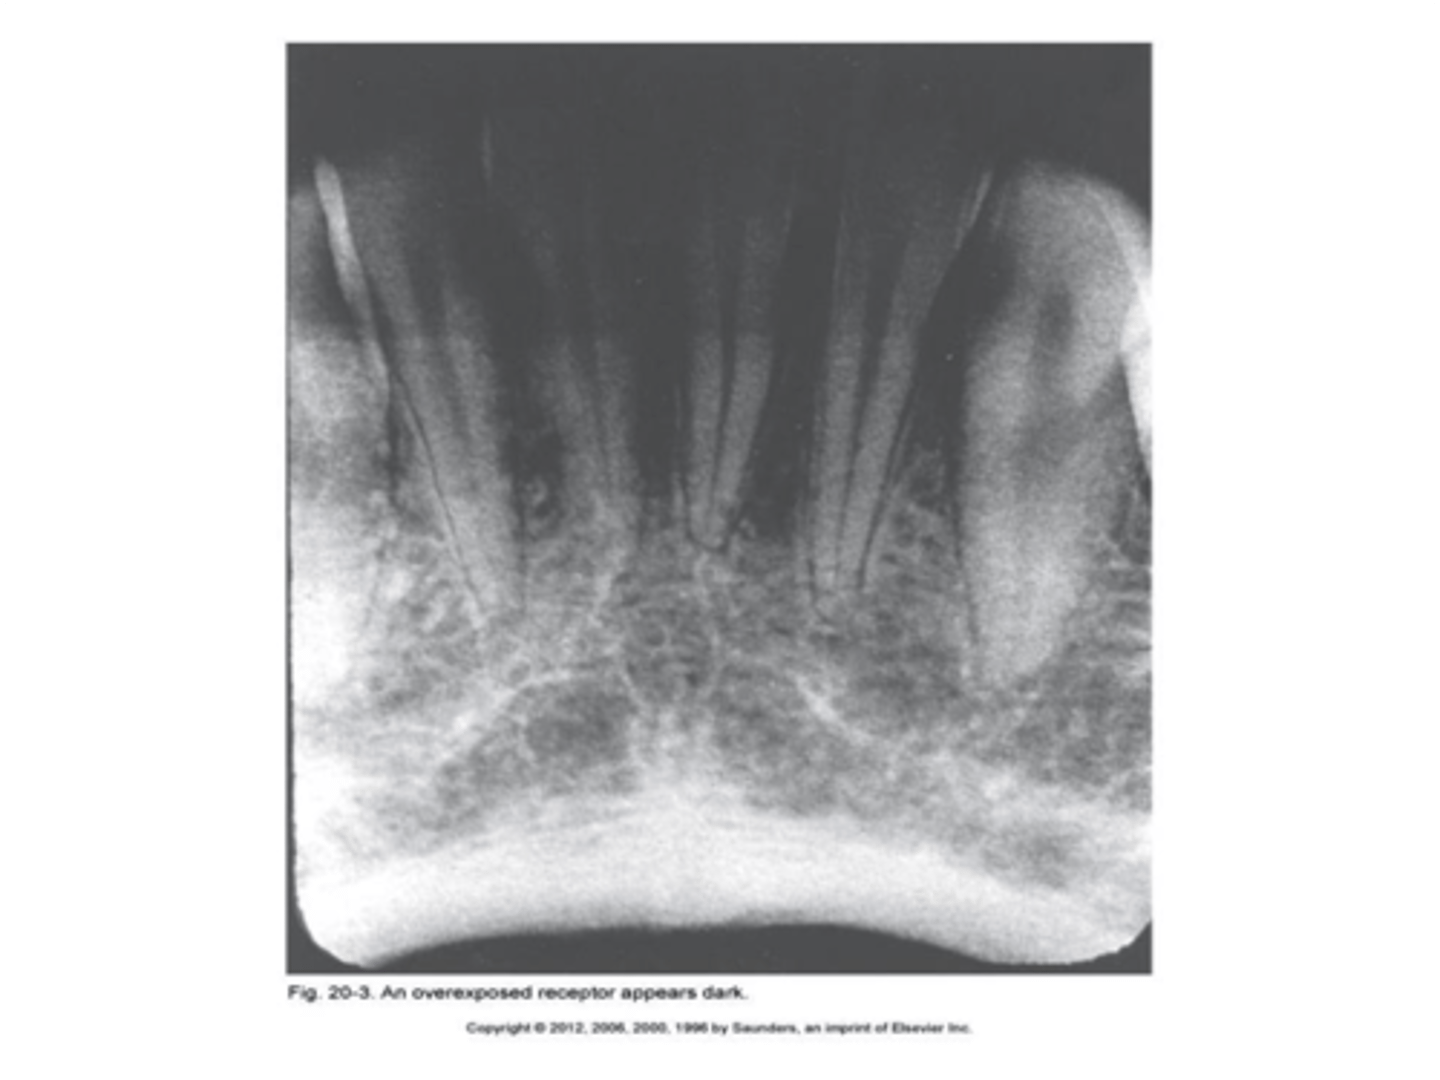

Overexposed receptor

Image appears dark.